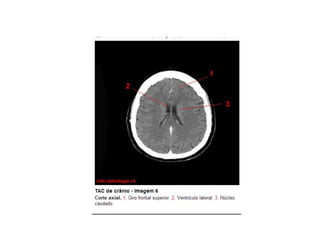

Anatomia E Protocolo Tomografia Computadorizada de Crânio PPT

Anatomia Seccional do Crâneo em Tomografia Computadorizada PPT